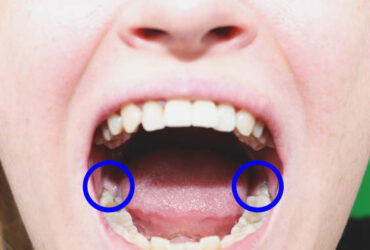

ฟันคุดคือ ฟันกรามซี่ในสุด ทั้งหมด 4 ซี่ บน ล่าง ซ้าย ขวา ไม่สามารถขึ้นได้ตามปกติเพราะพื้นที่ไม่เพียงพอให้ฟันสามารถขึ้นมาได้ บางซี่อาจจะโผล่ขึ้นมาเล็กน้อย และบางซี่ถูกฝั่งอยู่ในกระดูดขากรรไกร อาจจะขึ้นตรง เอียงหรือนอนในแนวราบส่วนใหญ่ฟันคุดมักพบว่าอยู่ที่ฟันกรามซี่ล่างในสุดและพบมากสุดในช่วงอายุ ประมาณ 16 – 25 ปี หรืออาจจะช้ากว่านั้น